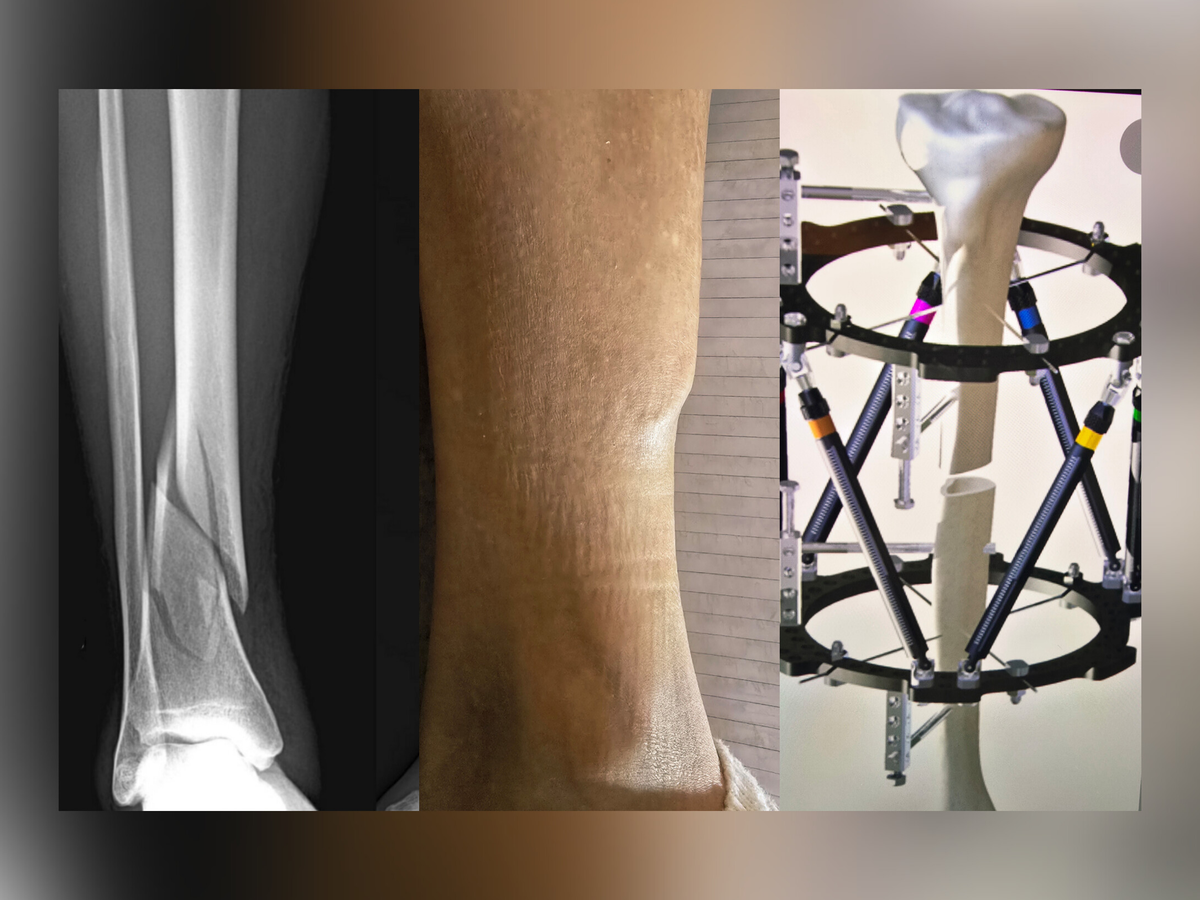

After extensive evaluations, doctors determined that corrective surgery is now the only option. She will need a complex tibial reconstruction using a Taylor Spatial Frame, an external fixation device that slowly grows new bone and rotates the leg back into its correct anatomical plane. This is not a short process — she will need to wear the frame for 12 to 15 months, followed by additional rehabilitation.